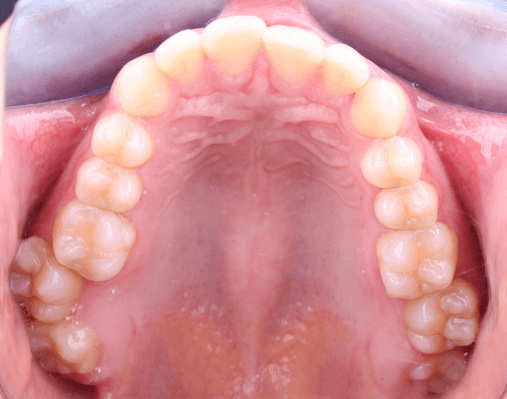

Intraoralmente, la paciente presenta una relación molar y canina clase I bilateral (figura 4), con apiñamiento leve en el sector anterior de ambas arcadas (figura 5). Se observó un overjet de 2 mm y overbite de 3 mm. Los segundos molares superiores se encontraban ligeramente vestibularizados y fuera del arco, configurando una mordida telescópica (figura 6). Esta posición contribuía a la discrepancia oclusal y a la disfunción funcional referida.

Figura 6. Fotografía oclusal superior.

El análisis de modelos reveló un exceso dentario en el maxilar superior de 1 mm (0.5 mm anterior y 0.5 mm posterior) según Bolton. La discrepancia perimetral fue de 10 mm en el maxilar superior y 8 mm en la mandíbula, en el contexto de un apiñamiento leve.